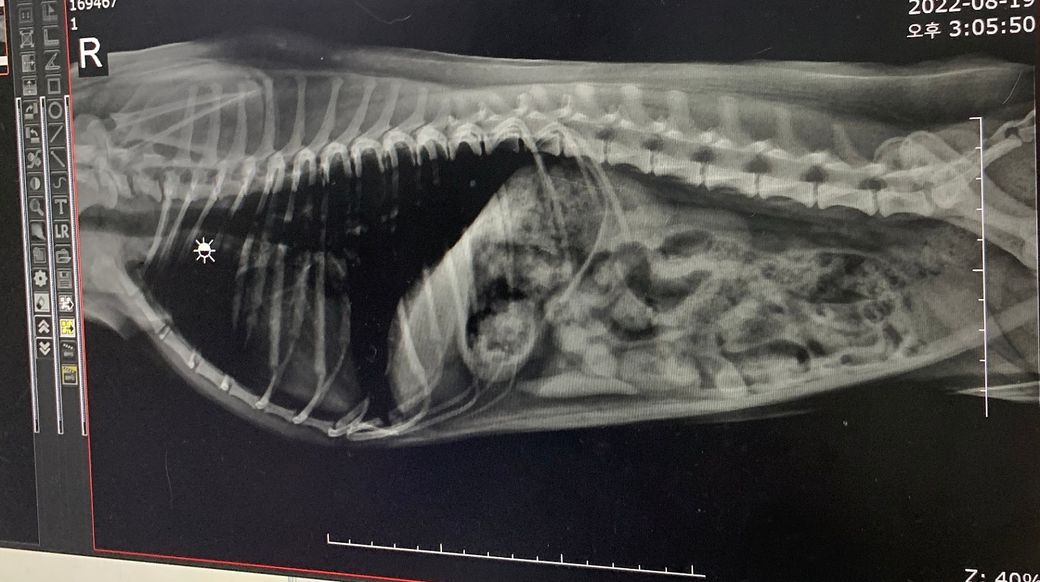

병원에서 간 크기 엑스레이를 찍었는데 간이 작단 말씀이 있으시고 구체적으로 잘 못들어서요 ㅠㅠ

혹시 한번 봐주실 선생님 계시나요?

간크기가 평균 일반 아이들 크기에 비해 많이 작은 편인지 아니면 적당히 작은 편인지 궁급합니다.

정상의 1/2 정도 크기 밖에 안되는지요? 아니면 그보다 더 한가요?

엑스레이로 간의 크기를 평가할때 기준은 위의 사진처럼 빨강색으로 표시된 위내에 있는 가스를 보고 축을 세운 그 기준이

늑골의 축인 노란색과 평행한것을 기준으로 삼습니다.

그래서 이 노란색 축과 평행하면 정상, 노란색 축보다 뒤로 밀려 보이면 간이 커진것, 노란색 축쪼으로 당겨져 보이면 작아진것으로 측정합니다. (많은 방법이 있지만 가장 간단하고 일반적으로 많이 사용하는 방법입니다.)

그것에 비해 첨부하신 사진을 보면

전형적으로 늑간 축쪽으로 위축이 이동한 상태 즉, 소간증 양상을 보이고 있습니다.

품종을 고려하더라도 상당히 감소한것으로 판단됩니다.

간이 다른 개체에 비해 얼마만큼 감소했는지는 CT를 통해 확인하는것이지 방사선 검사를 통해 확인하는것은 아닙니다.

다만 정상인 상태보다 위축의 각도를 고려할때 길이가 1/2 정도로 감소했으니 간크기 즉 용적인 세제곱만큼 감소했다고 가정한다면

1/8로 감소한 상태라고 해석하는게 비공식적으로는 합당한 추정입니다.

심장도 크기가 줄어 있고 흉골에 떠있을만큼 크기가 줄어든 상태인점, 말티푸인점, 4세정도의 중년령인점 등을 고려할때 에디슨병과 같은 내분비계질환이나

콩팥의 크기 증가도 동반되어 관찰되는점을 고려할때 PSS나 MVD 등을 고려해야 하고 간경화의 가능성도 같이 고려되어야 하는 상태로 생각됩니다.